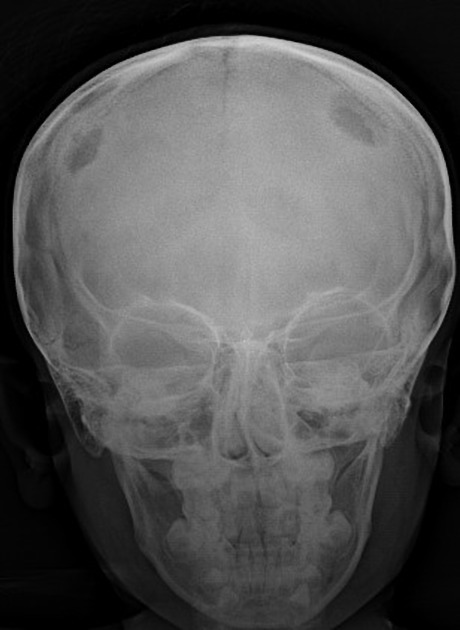

Copper beaten skull

A

Primary:

Raised intracranial pressure in children.

Other:

Craniosynostosis

Obstructive hydrocephalus

Hypophosphatasia

Intracranial masses